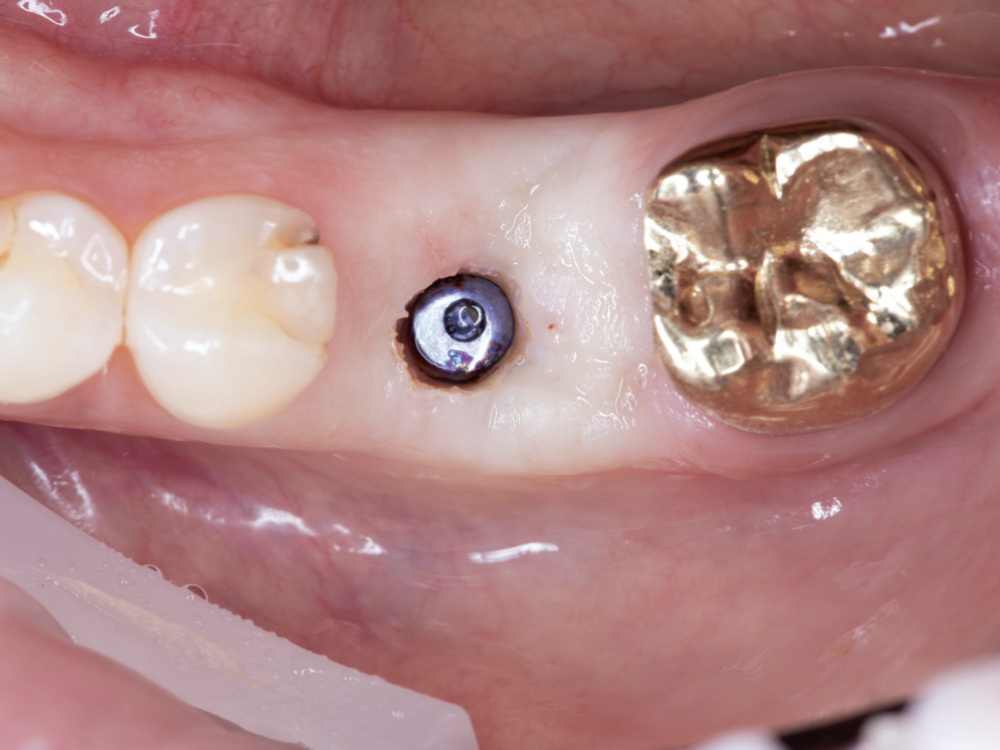

Verify Complete Scan Body Seating

Verify Complete Scan Body Seating. Confirm the scan body is fully seated to the implant before scanning — how it seats is precisely how the final restoration will seat. Use a radiograph if there is any question about complete seating, as an incompletely seated scan body will result in a restoration that does not fit, regardless of scan quality. Apply firm finger pressure or use a seating instrument, then verify there is no rocking or movement. Check for any tissue interference preventing complete seating and address it before scanning.

Capture the Surrounding Soft Tissue Immediately

Capture the Surrounding Soft Tissue Immediately. Scan the peri-implant soft-tissue architecture as soon as the scan body is placed, before the tissue collapse occurs. Gingival tissues begin to collapse and distort within minutes of scan body insertion, and the initial tissue contours are critical for creating proper emergence profiles. Work efficiently but thoroughly to document the tissue topography in its most accurate state.

Implant post scan on left side of mouth